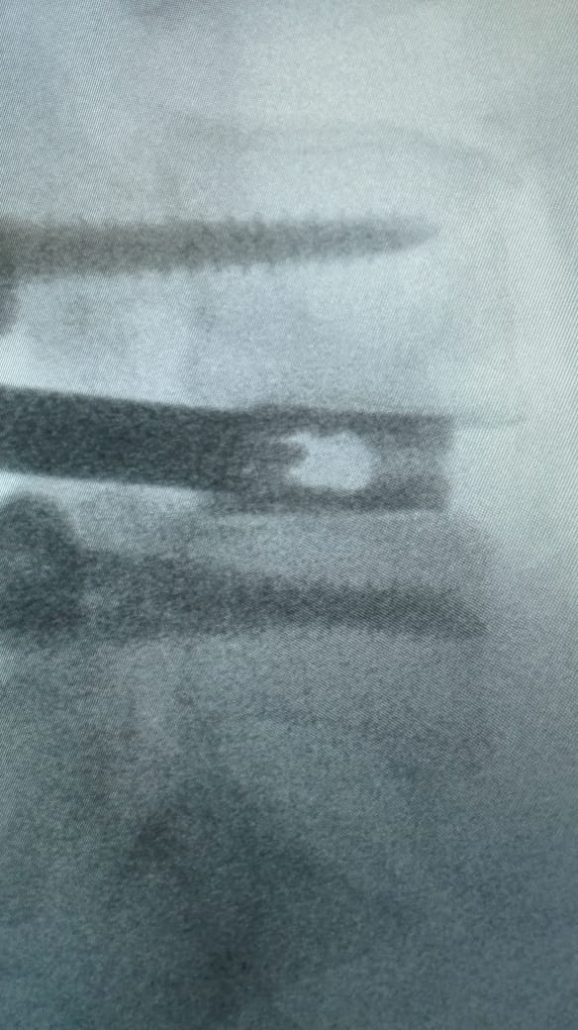

Latest Spine Fixation Technique